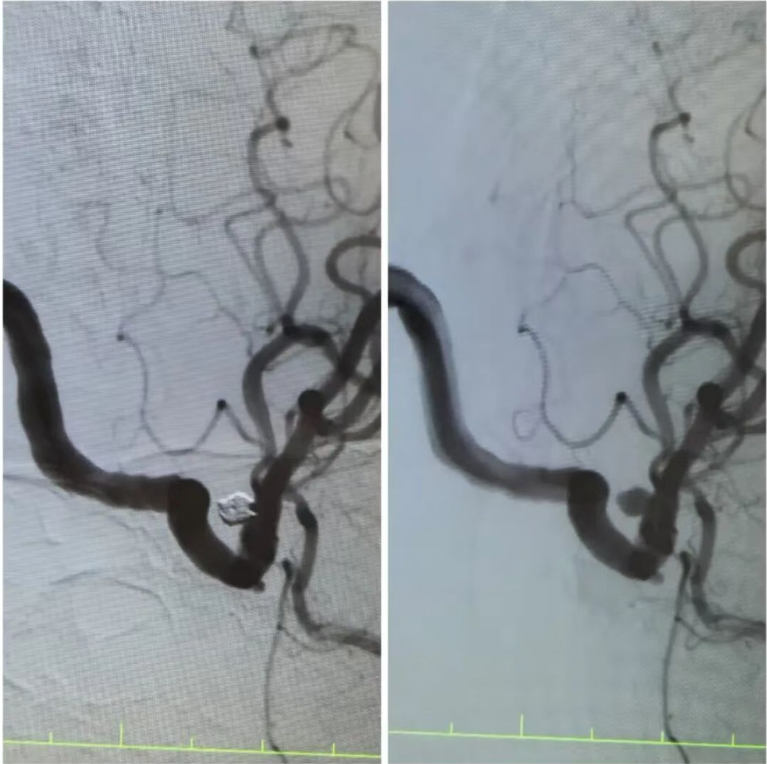

在王阿姨的造影檢查上,可清晰地看到動(dòng)脈瘤的形態(tài):如同血管上懸掛的“小囊袋”,薄如蟬翼的瘤壁隨時(shí)可能再次破裂?!伴_顱手術(shù)創(chuàng)傷大,老人基礎(chǔ)疾病多,風(fēng)險(xiǎn)極高,而介入栓塞術(shù),能通過股動(dòng)脈穿刺的“鑰匙孔”路徑,精準(zhǔn)封堵動(dòng)脈瘤?!笔中g(shù)團(tuán)隊(duì)反復(fù)推演方案,最終選定顱內(nèi)動(dòng)脈瘤栓塞術(shù)——用纖細(xì)的微導(dǎo)管將彈簧圈送入動(dòng)脈瘤腔內(nèi),像“織網(wǎng)”一樣填充瘤腔,隔絕血流沖擊,從根源上消除破裂風(fēng)險(xiǎn)。

手術(shù)臺上,丁院長握著導(dǎo)管在血管中精準(zhǔn)穿梭,如同在迷宮中尋找唯一的出口。當(dāng)微彈簧圈依次填入動(dòng)脈瘤,造影顯示瘤腔被完美“封堵”,載瘤動(dòng)脈血流恢復(fù)通暢,這枚困擾老人許久的“炸彈”,終于被安全拆除。術(shù)后的王阿姨頭暈頭痛癥狀消失,胸悶氣短的老毛病也因身心狀態(tài)改善而減輕。“感覺腦袋里的‘炸彈’沒了,整個(gè)人都輕快了!”